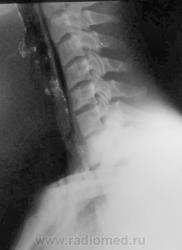

Шейный кифоз настораживает.Отсутствие легочного рисунка в верхней доле левого легкого с краем легкогоЭмфизема мягких тканей шеи..Согласна с коллегой.Пару лет назад по кифозу ШОП, увеличению превертебрального пространства и столбу воздуха поставили разрыв пищевода.Дали  контраст-подтвердили.

Затекания контраста за пределы пищевода на представленных рентгенограммах не выявлено. Нет фазы тугого заполнения. Левосторонний пневмоторакс.

Да, ЛОРа 100% надо на консультацию, т.к. барий затек не туда.